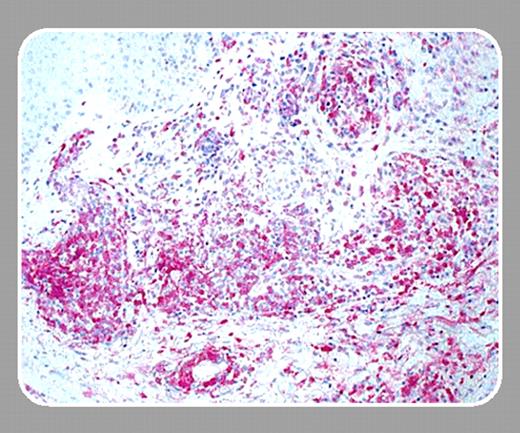

Cutaneous T-cell lymphomas represent a tumor with a defined target, the somatically rearranged T-cell receptor (TCR), that should represent a tumor-specific immunologic target analogous to the idiotype (Id)-specific target of B-cell lymphomas. The Id antigen on B-cell lymphomas has been targeted by Levy and others using a variety of vaccine approaches and large prospective clinical trials of this strategy are ongoing. The secreted antibody associated with myeloma has also been demonstrated to be processed and presented on malignant B cells and could be recognized by antigen-specific T cells.1 Although much less common than B-cell malignancies, the TCR on T-cell malignancies also represents an attractive immunotherapy target. Unfortunately, the TCR is not secreted and capturing the antigen from an individual's tumor for the creation of a vaccine usually involves creating a whole tumor lysate.FIG1

Maier and colleagues (page 2338) performed this experiment, vaccinating 10 cutaneous T-cell lymphoma patients with tumor lysate pulsed onto autologous dendritic cells (DCs) loaded with tumor lysate and given by intranodal injection.2 Intranodal injection appears to be a important route of delivery since the initial observation that intravenous and subcutaneous delivery in humans lead to little trafficking to lymph nodes, whereas only a fraction of DCs injected into the dermis trafficked to draining lymph nodes.3

In this report, Maier and colleagues have shown the induction of antigen-specific T-cell responses and clinical response in patients with cutaneous T-cell lymphoma. The authors noted that delayed-type hyper-sensitivity to the tumor lysate was increased in treated patients and recognition of autologous tumor cells by peripheral blood mono-nuclear cells (PBMCs) following vaccination compared with PBMCs obtained prior to vaccination as determined by cell proliferation and cytokine release assays. Significant recognition was notable in 3 patients, all of whom had a clinical response (1 complete and 2 partial responses). One element that was not specifically addressed by this study was whether an immune response to the specific TCR of each tumor was induced.